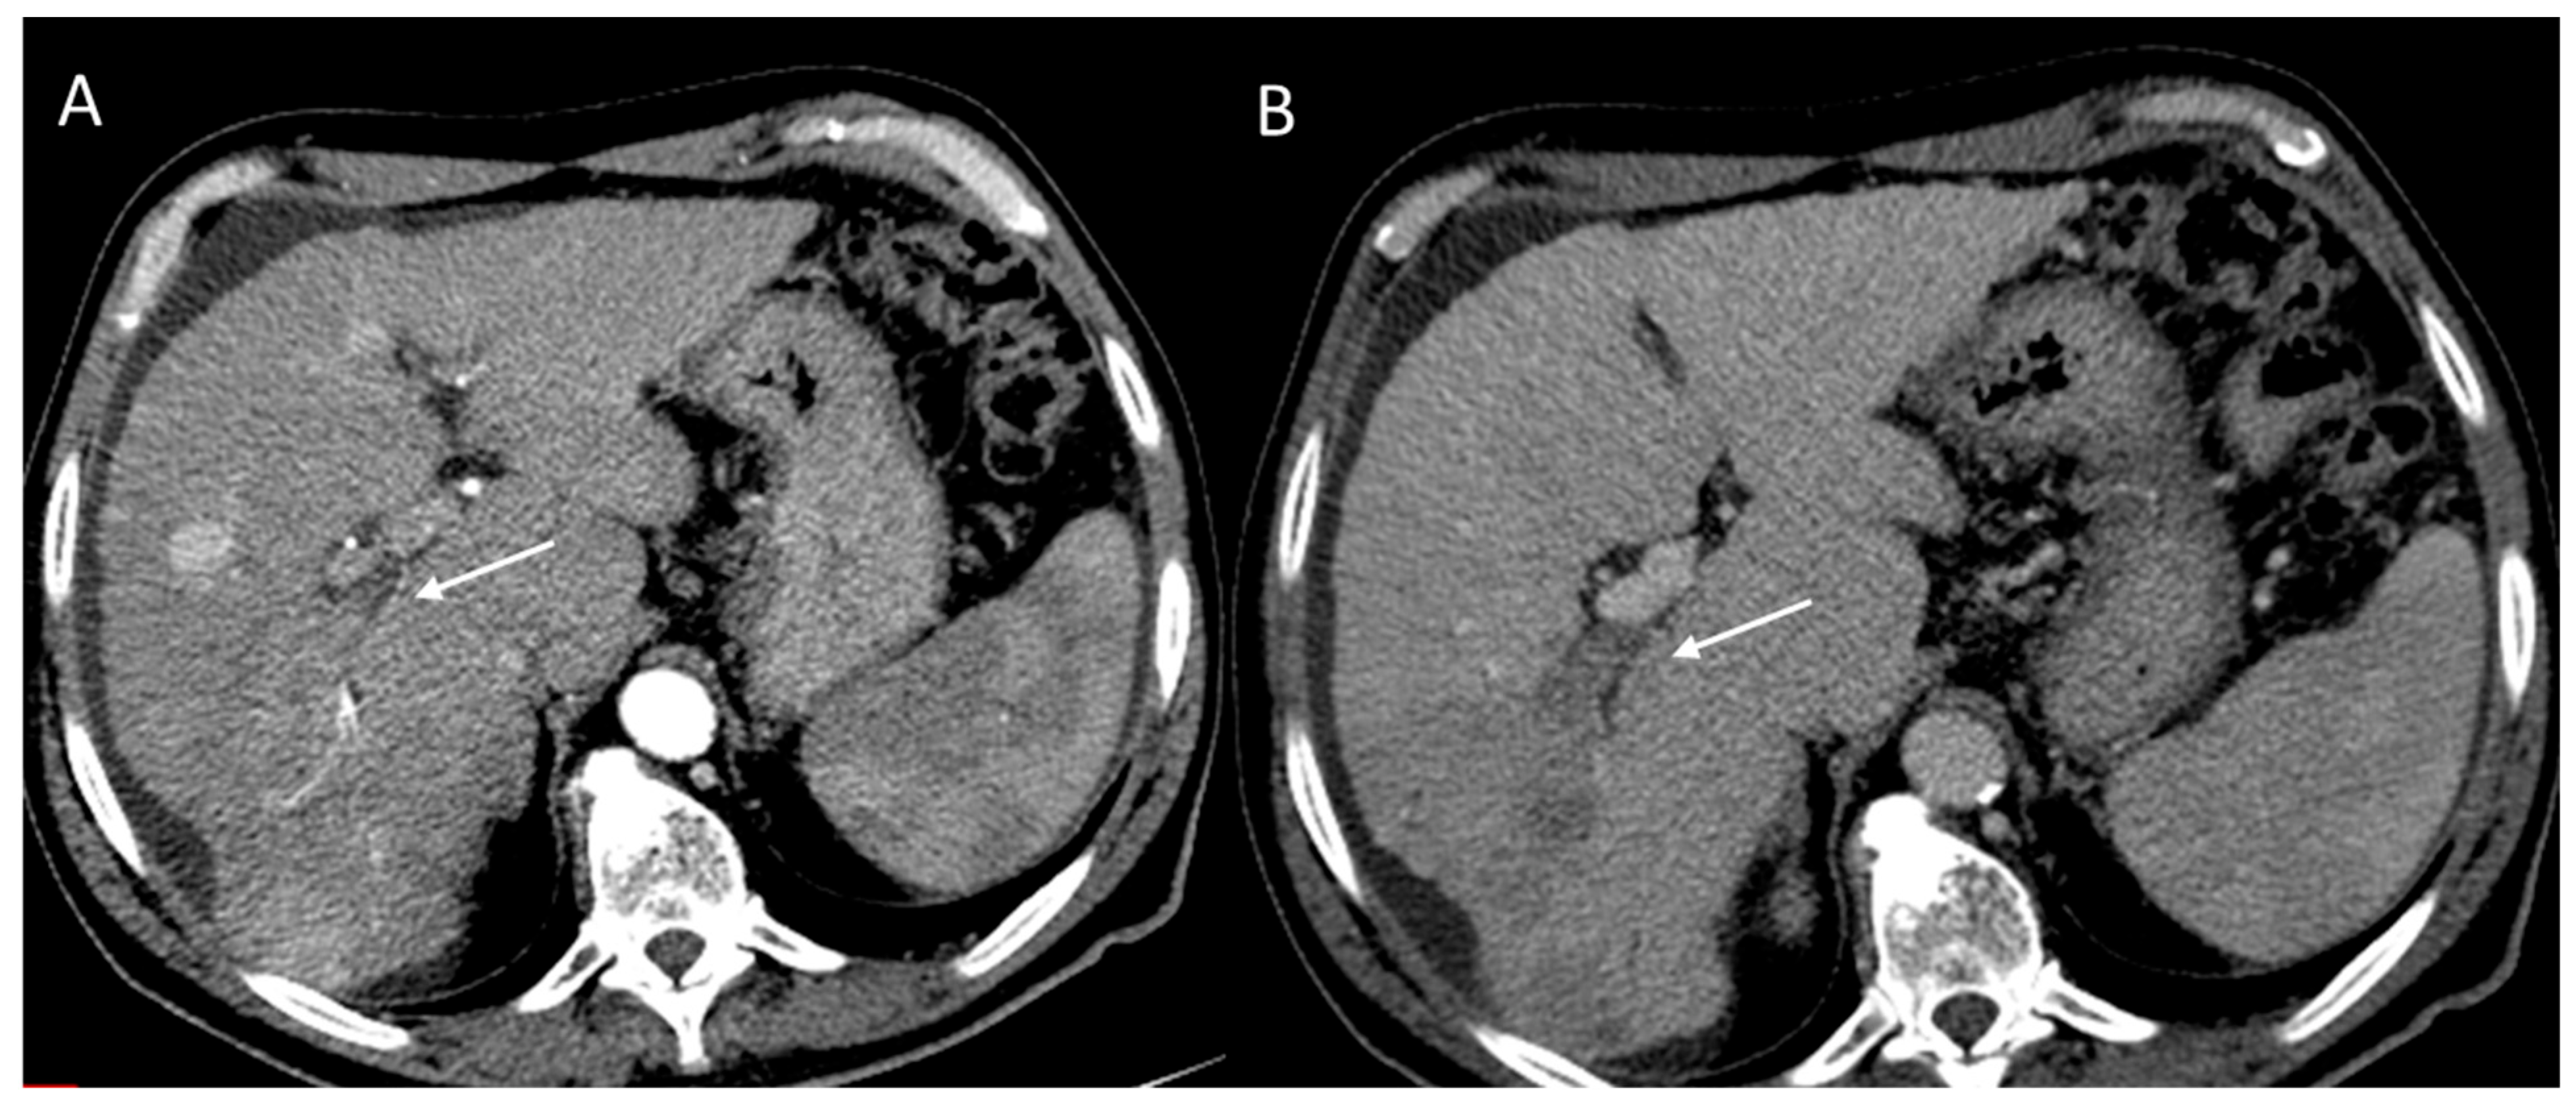

2.2.3. HCC Diagnosis

2.2.4. Ancillary Features